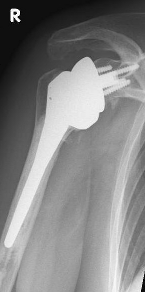

Conventional stem prostheses for omarthrosis and acetabular wear

right: anatomical shoulder prosthesis with glenoid replacement (Affinis type, Mathys company)